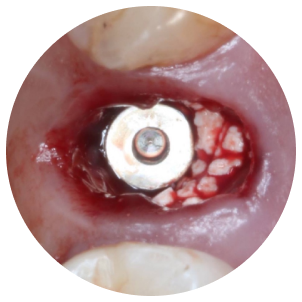

代表的な再生療法のひとつが「GBR(骨誘導再生法)」です。骨が不足した部位に自家骨や人工骨を補填し、特殊な膜(メンブレン)で覆うことで、骨の再生を促しインプラントの土台を築く方法です。

また、上顎奥歯など骨が特に薄い部位には「サイナスリフト(上顎洞底挙上術)」が適応されます。上顎洞と呼ばれる空洞の底を持ち上げ、その下に骨を造成することで、十分なインプラント埋入スペースを確保することが可能になります。

これらの高度な再生治療は、歯科用CTや精密シミュレーション技術、そして確かな経験を持つ術者による対応が前提となります。

これは、虫歯や歯周病などで抜歯が必要になった際、その当日にインプラントを埋め込む方法です。従来であれば、抜歯後に歯ぐきや骨の治癒を数ヶ月待ったうえで次のステップへ進んでいましたが、この方法を用いることで、治療期間を短縮できるほか、手術の回数も抑えられます。

炎症の有無や骨の状態、歯ぐきの厚みや形など複数の条件を慎重に確認する必要があります。

大杉歯科医院では、CTや口腔内検査によって十分な診査を行い、適応可能と判断できた方にのみご提案しています。